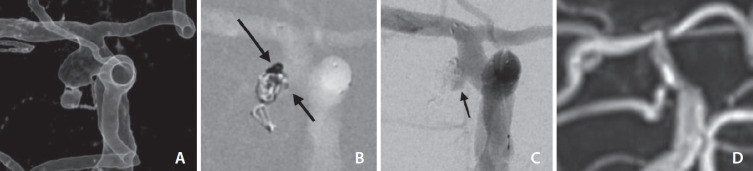

脉络膜前动脉(AChA)供应与上下肢运动功能有关的皮质脊髓束。发生在 AChA 的动脉瘤并不常见,而且 AChA 的受累模式多种多样。因此,处理 AChA 动脉瘤会带来神经功能缺损的高风险。我们报告了与未破裂 AChA 动脉瘤线圈栓塞术结果相关的技术问题。我们的研究获得了机构审查委员会的批准。在过去两年中,我们连续对 18 名(6 男 12 女,年龄 32-68 岁)未破裂 AChA 动脉瘤患者进行了栓塞治疗。我们介绍了技术细节、患者术前术后状况、血管造影结果以及平均随访 12 个月(3-25 个月)的复发情况。AChA 患者(18 人)接受了支架辅助卷曲术(14 人)、卷曲术(2 人)或仅支架植入术(2 人)。动脉瘤栓塞的技术策略包括:低位进入动脉瘤,支架支架连接(保护)线圈框架以阻断血流并避免影响 AChA 血流,以及通过微导管直接进行动脉瘤内血管造影。血管造影结果显示完全闭塞(11 例)、颈部残余(5 例)和囊部残余(2 例)。随访期间,有 2 例复发,其中 1 例需要再次手术。所有患者的临床状况均无变化(改良兰金量表评分=0),随访期间也未发生任何缺血或出血事件。AChA 动脉瘤可通过各种技术进行栓塞治疗。这些技术理念可提高 AChA 动脉瘤栓塞术的安全性并改善其疗效。

The anterior choroidal artery (AChA) supplies the corticospinal tract related to the motor function of the upper and lower limbs. Aneurysms arising at the AChA are not common and exhibit various patterns of involvement of the AChA. Hence, managing an AChA aneurysm poses a high risk of neurological deficits. We report technical issues related to the outcome of coil embolization for unruptured AChA aneurysms. We obtained Institutional Review Board approval for this study. In the past 2 years, 18 consecutive patients (6 males and 12 females, aged 32-68) with unruptured AChA aneurysms were treated using embolization. We present technical details, pre- and post-procedural patient statuses, angiographic outcomes, and recurrence during a mean follow-up period of 12 months (range 3-25). The patients with AChA (n=18) underwent stent-assisted coiling (n=14), coiling (n=2), or stenting only (n=2). The technical strategy for aneurysm embolization included a low-lying approach into the aneurysm, stent-strut abutting (protecting) coil framing to block inflow and avoid compromising AChA flow, and direct intra-aneurysmal angiography via a microcatheter. Angiographic results showed complete occlusion (n=11), neck remnant (n=5), and sac remnant (n=2). During the follow-up, there were 2 recurrences, and 1 of them required a re-procedure. All patients showed no change in clinical status (modified Rankin scale score=0) and did not experience any ischemic or hemorrhagic events during the follow-up period. AChA aneurysms can be managed through embolization using various techniques. Such technical concepts may enhance the safety and improve the outcomes of AChA aneurysm embolization.